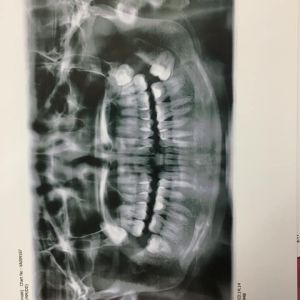

Răng cửa quá thưa thế này thì nên chọn niềng kim loại hay niềng Invisalign?

Theo tôi, niềng trong suốt Invisalign không phải là giải pháp phù hợp cho trường hợp của bạn. Không phải ai cũng phù hợp với niềng Invisalign vì loại niềng này chỉ nắn chỉnh răng được ở mức độ nhẹ và điều trị các vấn đề đơn giản mà các răng cửa của bạn lại quá thưa. Kể cả với niềng mắc cài thông thường thì việc khắc phục vấn đề của bạn cũng khá là phức tạp và mất nhiều thời gian. Hơn nữa, bạn còn có tật đẩy lưỡi nữa và nếu không sửa được thì kể cả khi đã trải qua quá trình niềng và khoảng hở đã được đóng lại thì các răng này vẫn rất dễ bị thưa ra trở lại. Do đó, bạn nên cố gắng sửa thói quen này và sau khi tháo niềng thì cần đeo hàm duy trì vĩnh viễn. Ngoài niềng răng ra thì bạn còn có thêm một lựa chọn nữa đơn giản hơn là dán composite hoặc dán sứ Veneer để che đi khoảng hở và làm cho các răng cửa có tỉ lệ cân xứng hơn với các răng xung quanh.